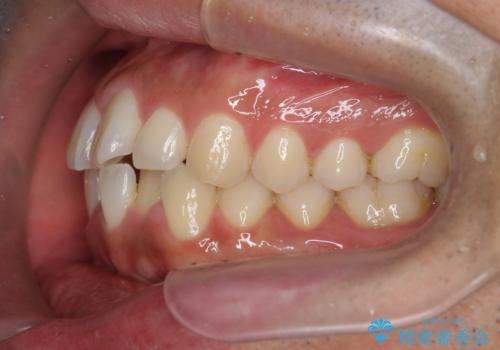

- 前歯のガタつきをきれいにしたい、と矯正治療を希望され来院されました。

マウスピース矯正インビザラインを用いてガタつきをきれいに並べていきます。

外側に傾斜していた前歯の角度も良くなり、「前歯の見た目が良くなった。」、と喜んでいただくことができました。